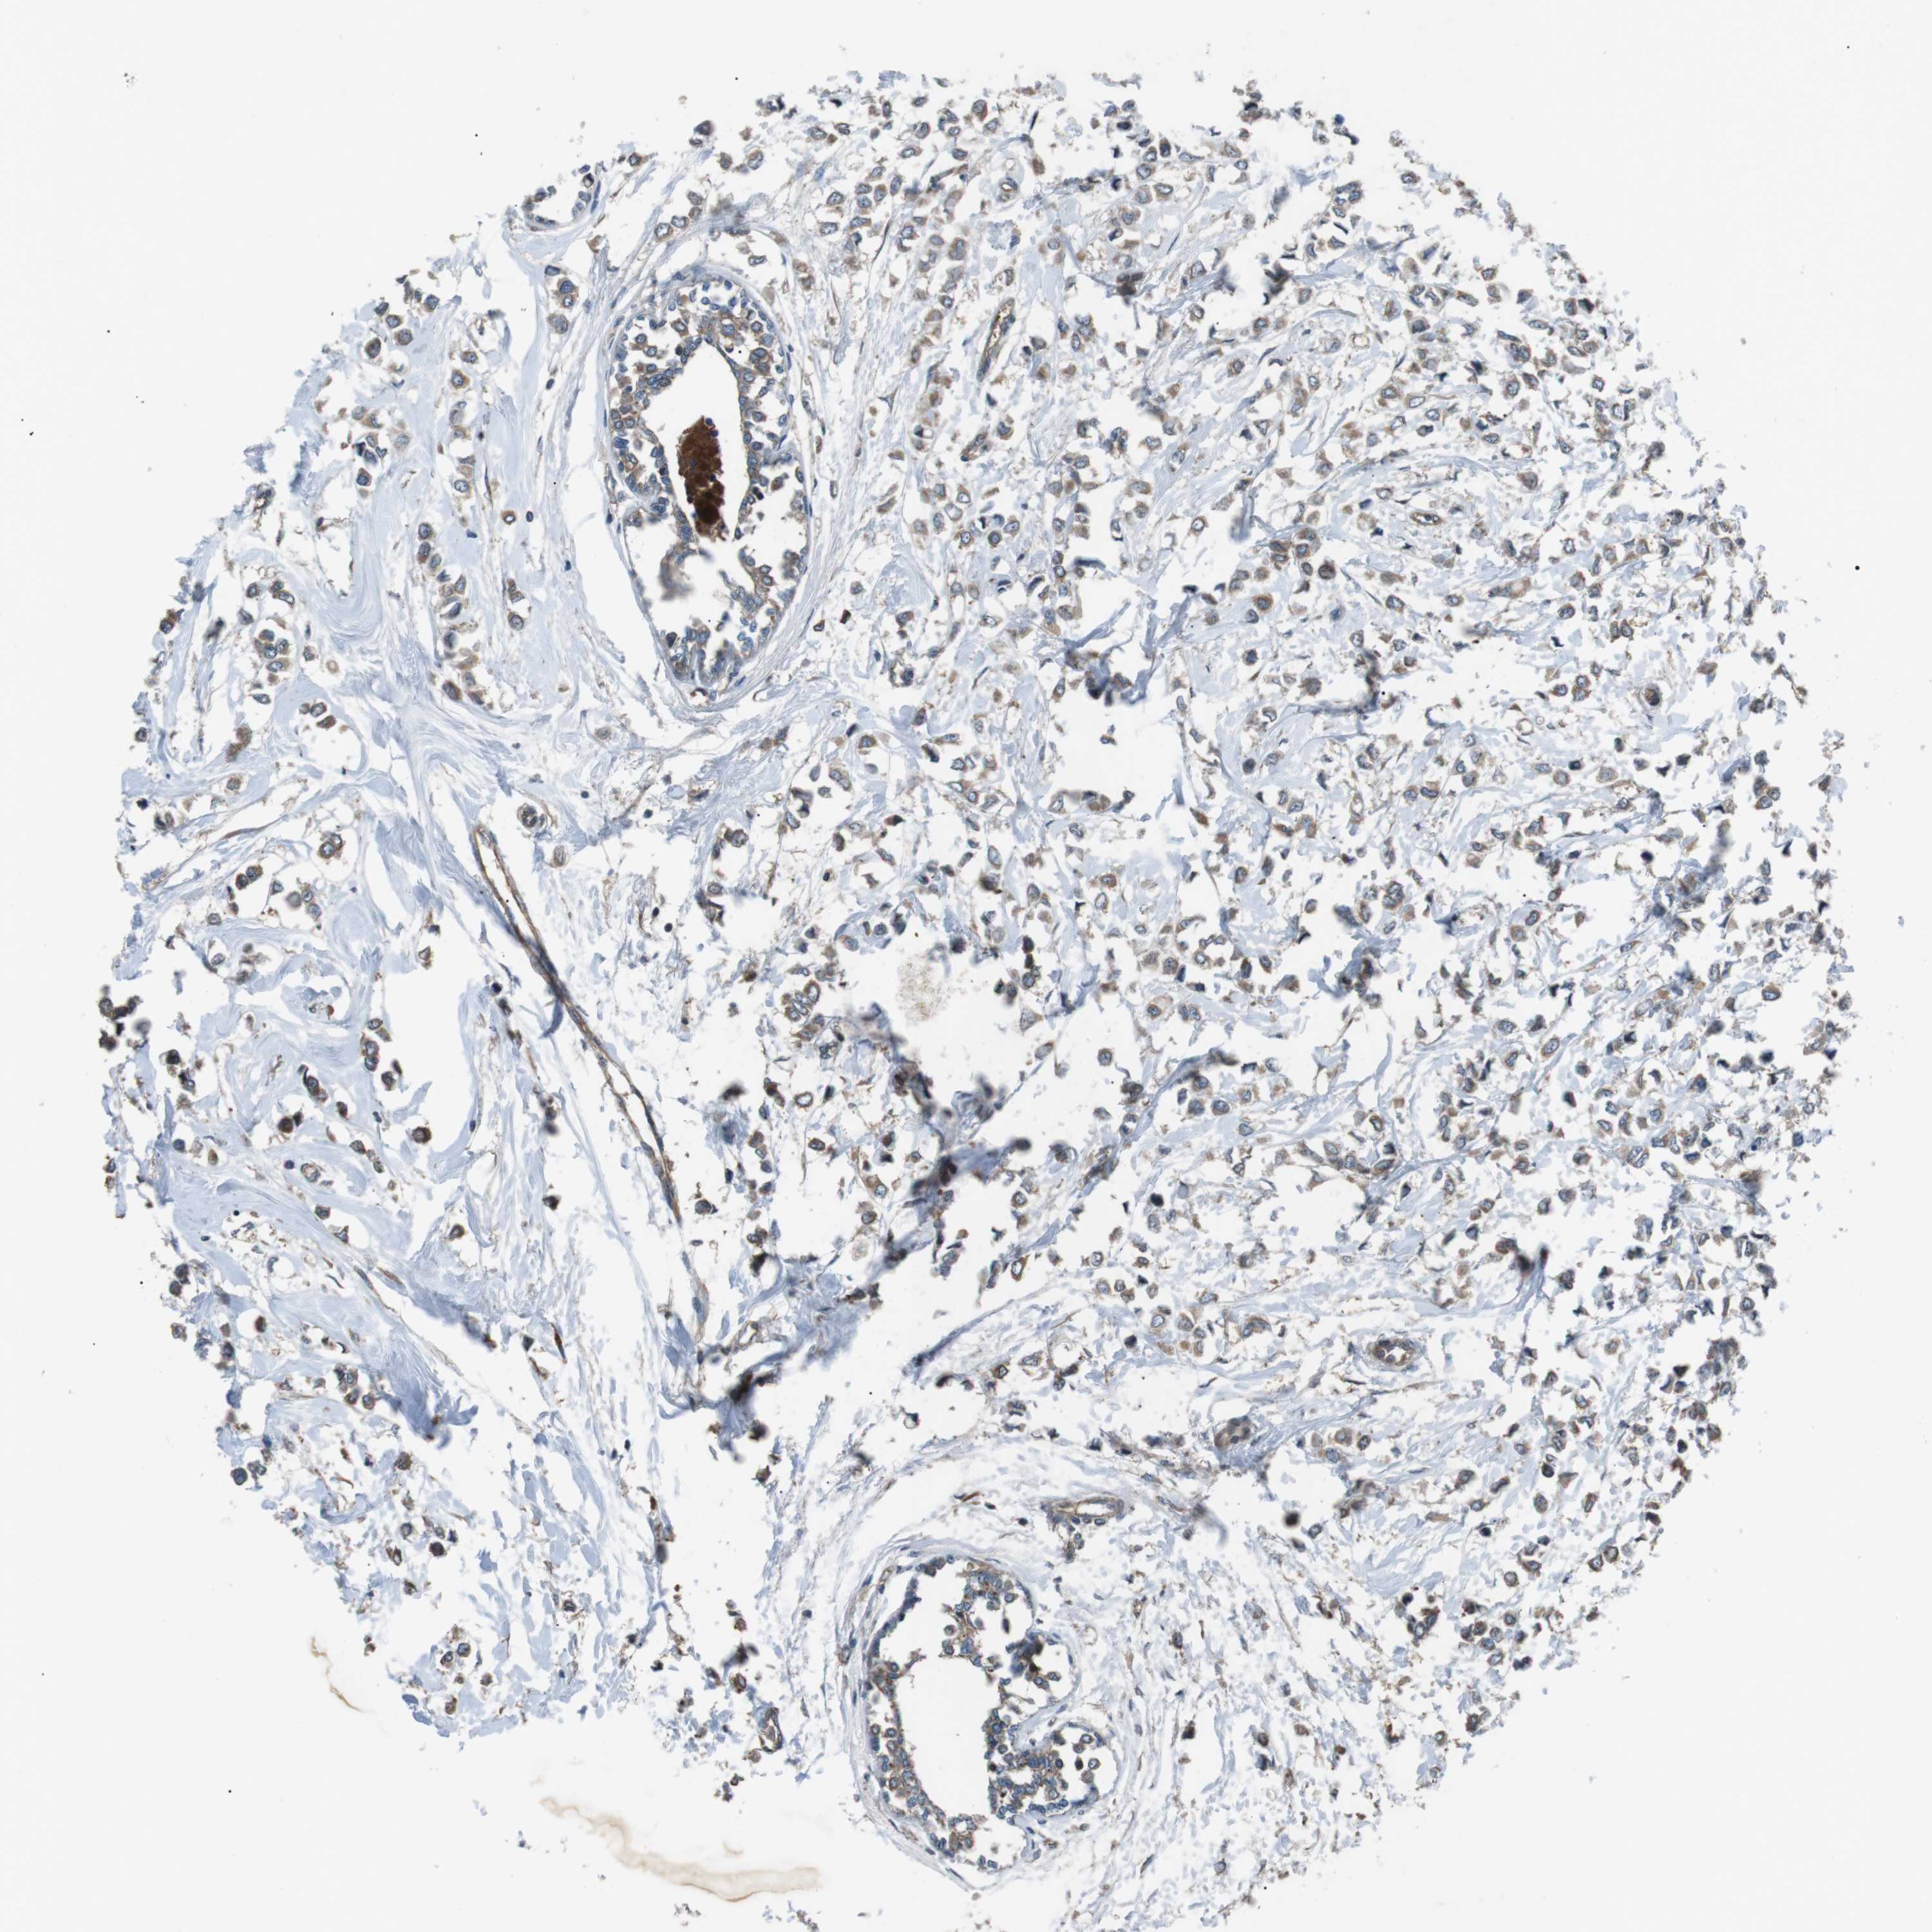

BRCA TCGA BRCA VALIDATION PROTEIN EXPRESSION

ANTIBODIES

AND

VALIDATION